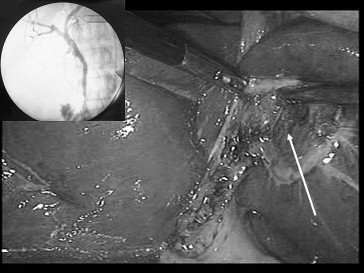

A 50-year-old woman with no medical history was admitted to our department with a history of 2 years' intermittent pain in her right upper abdomen, radiating to the back. There was no history of jaundice. The physical examination showed tenderness in the right upper quadrant of the abdomen without a Murphys sign. Laboratory findings demontrated normal rates of total bilirubin, alkaline phosphatase, γ-glutamyl transpeptidase, and C-reactive protein. Abdominal ultrasonography showed gallbladder stones without dilatation of the bile ducts. The patient underwent a laparoscopic cholecystectomy using the French position and four ports positioned as usual. The gallbladder was absent from its normal location. Medial exploration of the falciform ligament under the left liver revealed the gallbladder attached to a shallow fossa in the liver (Fig. 1). The cystic duct joined the common hepatic duct on the right side after making a hairpin bend, and the cystic artery originated from the right hepatic artery. Retrograde cholecystectomy was undertaken using electrocautery followed by intraoperative cholangiogram which showed neither dilatation of the bile ducts nor associated congenital anomalies of the biliary tree (Fig. 2). The patient was discharged on the first postoperative day, and had an uneventful postoperative period. Histological examination showed chronic cholecystitis.

Gallbladder lying to the left of the falciform ligament (white arrow) in ...

Figure 1.

Gallbladder lying to the left of the falciform ligament (white arrow) in relation to Segment III.